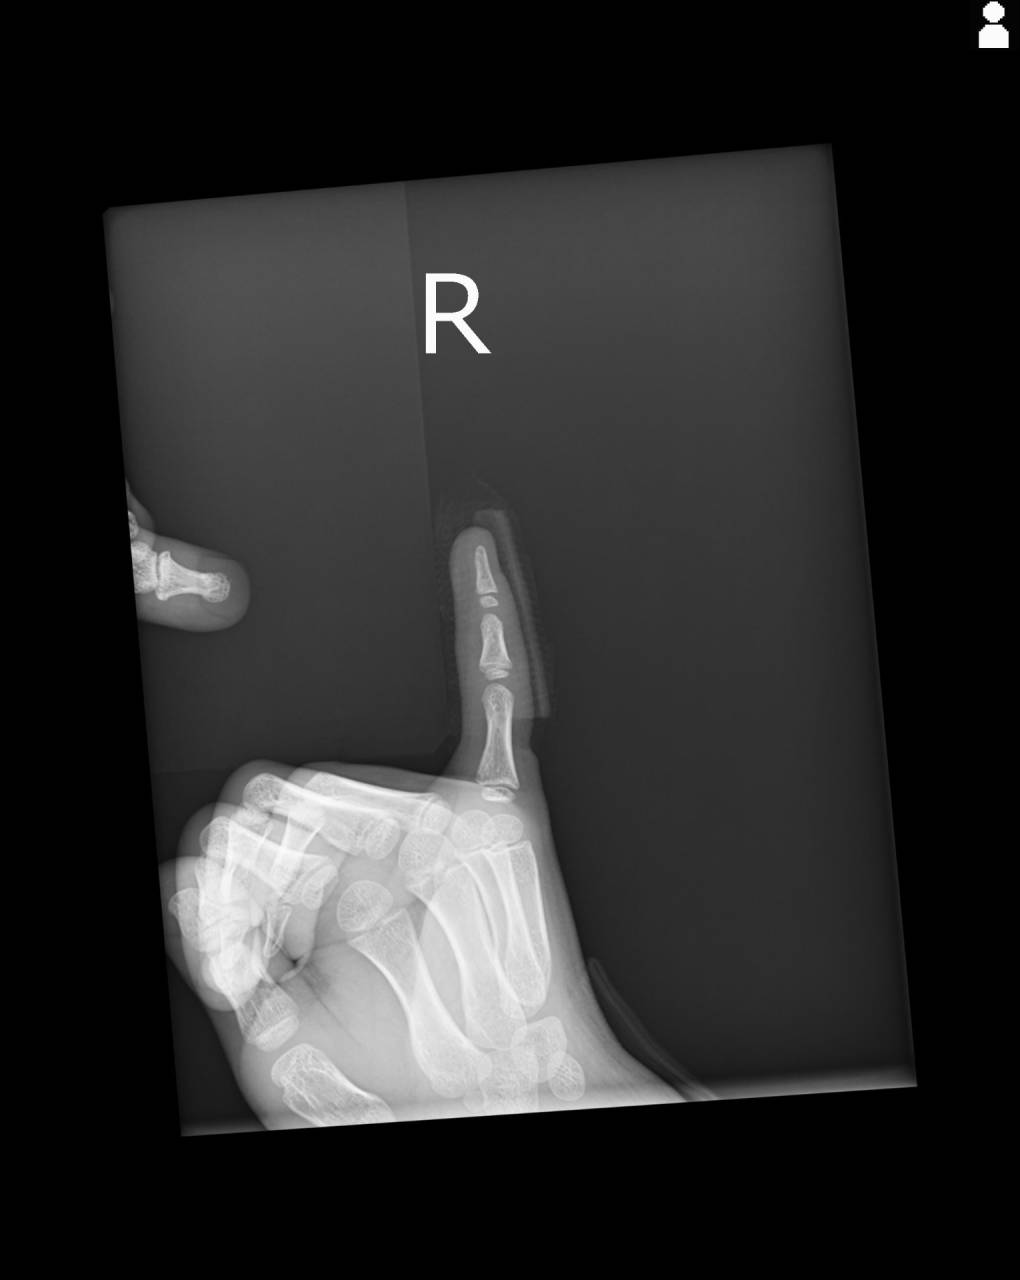

小学校低学年男子、格闘技の練習中に相手選手が自分の右手の上にのった際に右第5指を負傷したとのこと。

撮影した画像を確認すると1番圧痛のあった中節骨基部に骨折の疑いがあり、当整骨院が提携している病院にてレントゲン撮影を依頼しました。

撮影した画像を確認すると中節骨基部に骨のダメージがあることが分かり、今回のケースは骨折として施術を進めていきます。